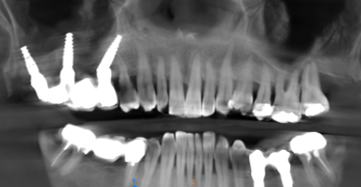

A partir de votre radio 3D réalisée au cabinet, nous lisons votre examen grace à des logiciels permettant une simulation précise du positionnement de vos implants dans l’os.

Cette vision 3D de l’implant dans l’os et en rapport avec les futures dents permet une reflexion « graftless », c’est a dire une implantologie nécessitant un minimum de greffe osseuse, donc plus rapide et moins mutilante.